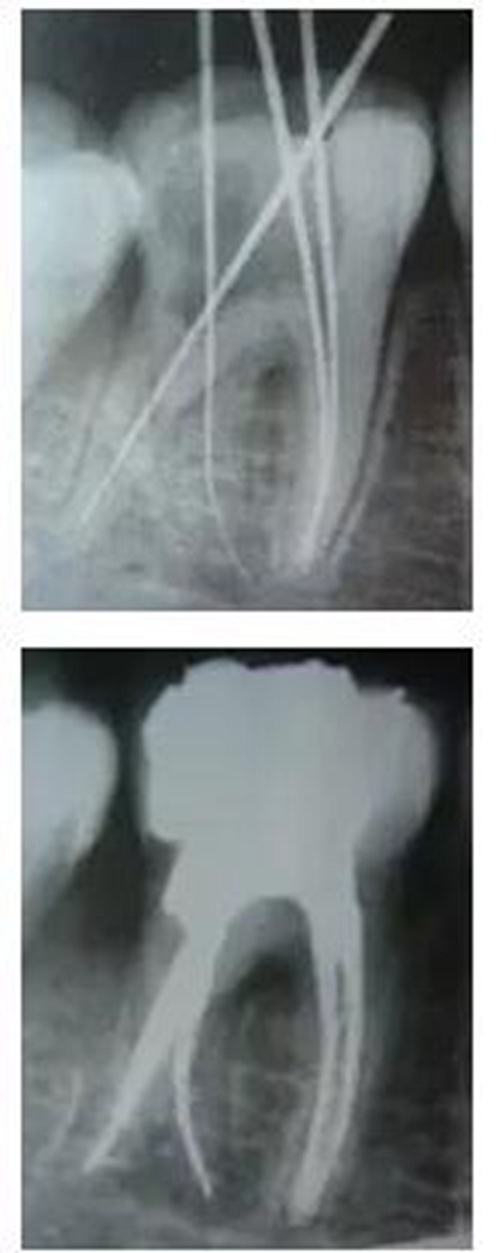

最后來玩一個(gè)根管治療質(zhì)量的評(píng)估——下圖是武大彭彬教授的一個(gè)病例,仔細(xì)觀察可以挑出一點(diǎn)問題,但問題事出有因!看看你的“眼力”如何——問題在那里?教授的專業(yè)水平是不用懷疑的,那么事出的原因可能是什么?

6.jpg

再次分享根管治療的點(diǎn)滴見解! 再次分享根管治療的點(diǎn)滴見解!

問題答案:這個(gè)病例的問題主要反應(yīng)在開髓的洞形修整,注意觀察該牙X-RAY的左側(cè)洞壁,如果常規(guī)情況制備成這樣是由于裂鉆破壞了洞壁和洞底所形成的臺(tái)階。如果評(píng)估根管治療的質(zhì)量那是要扣分的!但這個(gè)病例仔細(xì)觀察洞壁形態(tài)就可以看出:該病例屬于再治療的病例,因此還是屬于一個(gè)理想的病例。